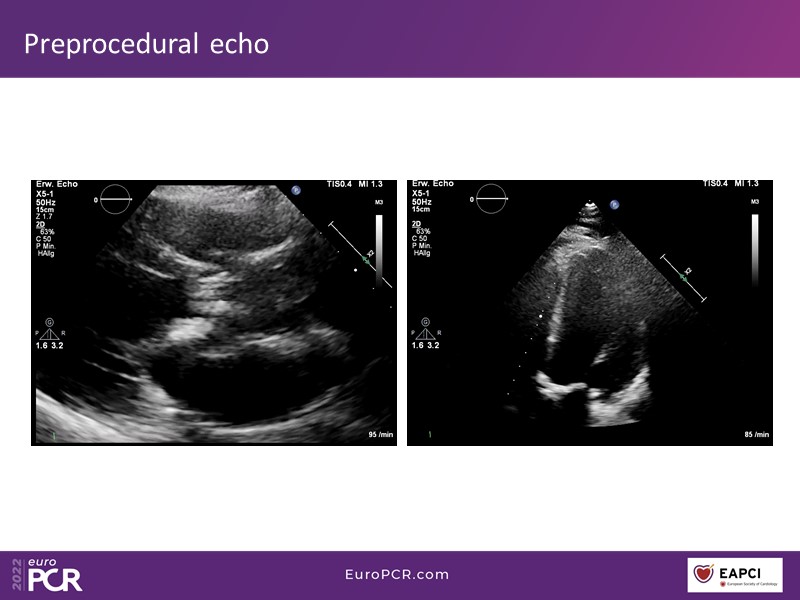

How to deal with challenging anatomies? Find answers in this EuroPCR 2022 session with case studies to explore and learn how to achieve optimal patient outcomes with Evolut platform, uncover practical tips and techniques to achieve implant precision and control, and become familiar with technical considerations and procedural execution of TAVI.